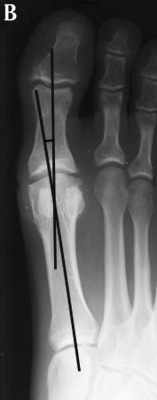

A. In hallux varus or adductus the HAV is less then 5º. B. In normal

subjects HAV is 5º to 15º . Hallux abducto valgus is mild when HAV is 16º to